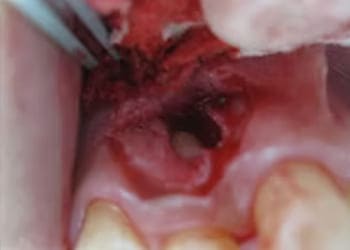

親知らずの治療は、基本的に抜歯が適応となります。

しかし、埋まった状態の親知らずの抜歯は難易度が高く、特に下顎の親知らずは顎の骨の中にある知覚神経(触覚や痛覚をつかさどる神経)や血管に近接しているため、抜歯後に唇や顔面皮膚の知覚異常が生じたり、抜歯部位から大量に出血したりする可能性があります。

もちろん、正常に萌出してきちんと噛めているものや、今後正常に萌出する可能性があるものについては、必ずしも抜歯する必要はありません。